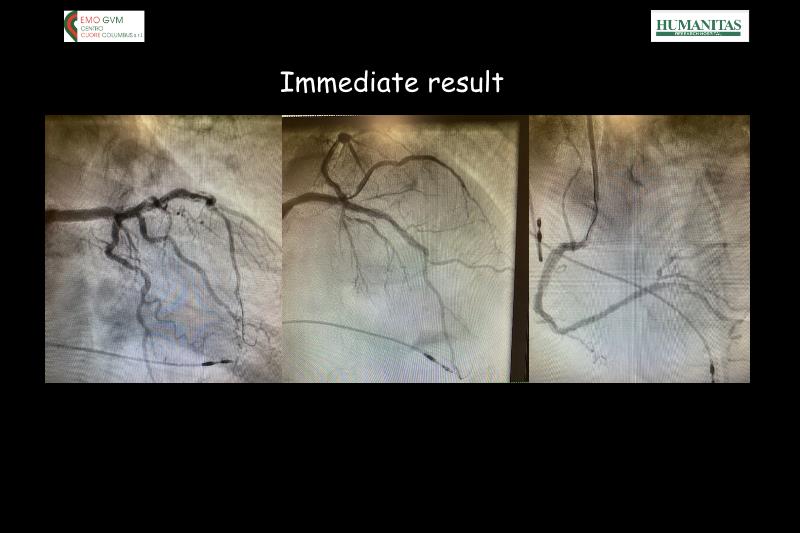

Watch this session to gain case-based insights on using DCBs in complex settings. Learn valuable tips and tricks for optimal DCB application, including the best timing and situations for their use. Discover how to effectively implement a hybrid strategy that combines DES and DCB when needed.

- To get a case based experience on how to use a DCB in complex settings

- To learn about tips and tricks on how and when to use a DCB: the ideal time and situation of DCB application in various complexities

- To utilise the hybrid strategy approach Combining DES and DCB when the situation demands